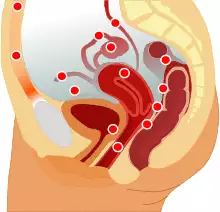

Drawing showing endometriosis.

Pain and infertility are common symptoms, although 20–25% of women are asymptomatic.[1]

Possible locations of endometriosis.

Most often, endometriosis is found on the: